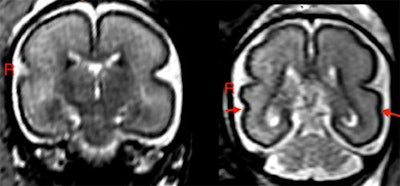

Compared to controls, the fTMS scores were significantly lower in fetuses exposed to alcohol (p = 0.007), and the right superior temporal sulcus of these fetuses was shallower (p < 0.001). This was true even for fetuses with mild alcohol exposure.

"As we show in our study, even low levels of alcohol consumption can lead to structural changes in brain development and delayed brain maturation," Kienast said.